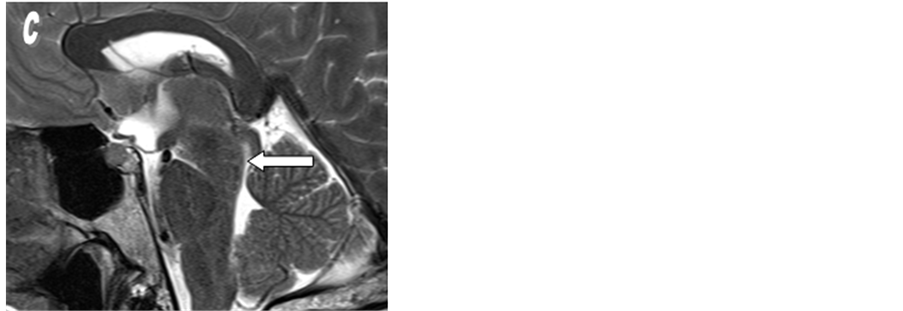

In view of persistent Orthostatic headache, Gadolinium Enhanced MRI of brain was done which showed sagging of the midbrain, pachymeningeal thickening; both supratentorial and infratentorial, enhancement and engorgement of the dural venous sinuses (Figures 1(a)-(c)).

Figure 1. MRI of the brain before and after IV Gd-DTPA injection. (a) & (b) Post contrast axial and coronal T1 weighted images with fat suppression showing diffuse pachymeningeal thickening and enhancement and engorgement of the dural venous sinuses (arrows in b). (c) Sagittal T2 weighted image showing sagging of the midbrain (solid Arrow).

Magnetic resonance imaging has revolutionized the diagnosis of ICH. The major abnormalities demonstrated on MR imaging studies in patients with ICH are diffuse thickening of the pachymeninges with Gadolinium enhancement, engorgement of venous sinuses, subdural fluid collections, enlargement of the pituitary gland, and downward displacement of the brain [13] . Meningeal enhancement in ICH is thick, linear, without nodularity, and involves the pachymeninges of both the infra- and supratentorial compartments without evidence of involvement of the leptomeninges (no abnormal enhancement around the brainstem, within the sylvian fissures, or in the depth of cerebral sulci) [14] . Our patient had characteristic MRI findings of enhancement of pachymeninges and brainstem descent. Intracranial hypotension if not controlled early, it can lead to cortical vein thrombosis, hyperprolactinemia, subarachnoid hemorrhage, subdural hematoma, cranial nerve palsy [15] .